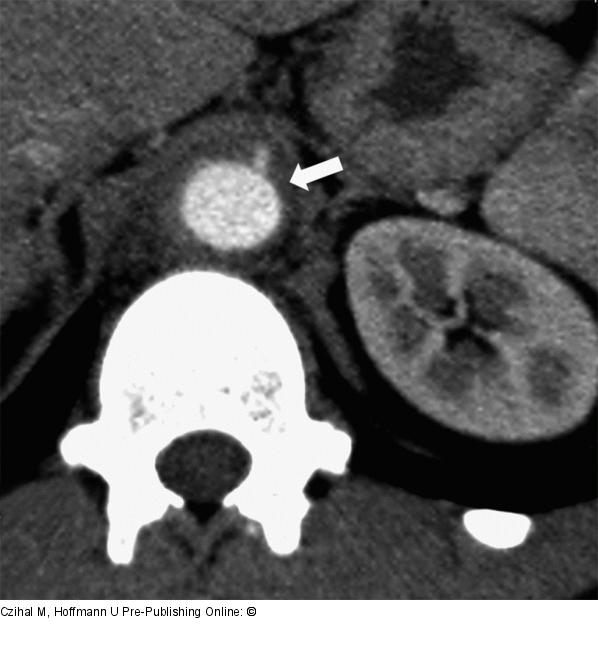

Abbildung 4: Aorta abdominalis - Pannus 25-jähriger Patient mit B-Symptomatik, dumpfen Rückenschmerzen und erhöhten systemischen Entzündungszeichen. CT-Angiographie mit Darstellung eines entzündlichen Pannus (Pfeil) im Bereich der suprarenalen Aorta abdominalis. Der Befund ist vereinbar mit einer chronischen Periaortitis. |